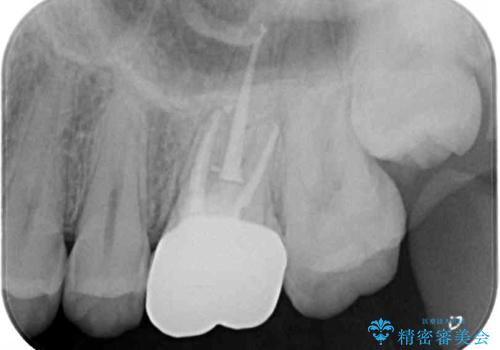

根管治療を実施した後、フルジルコニアクラウンに補綴することとしました。

前医での処置後、治療前には気にならなかった痛み続いていたようですが、当院での処置後は痛みが徐々に引いていき、治療から半年が経過した時点では全く違和感も感じなくなりました。

根管治療後のクラウンも、まるでもとの自分の歯のように自然な仕上がりとなり、患者様には大変満足していただけました。